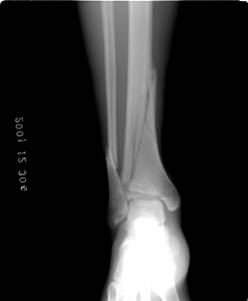

照片名称:右胫腓骨骨折